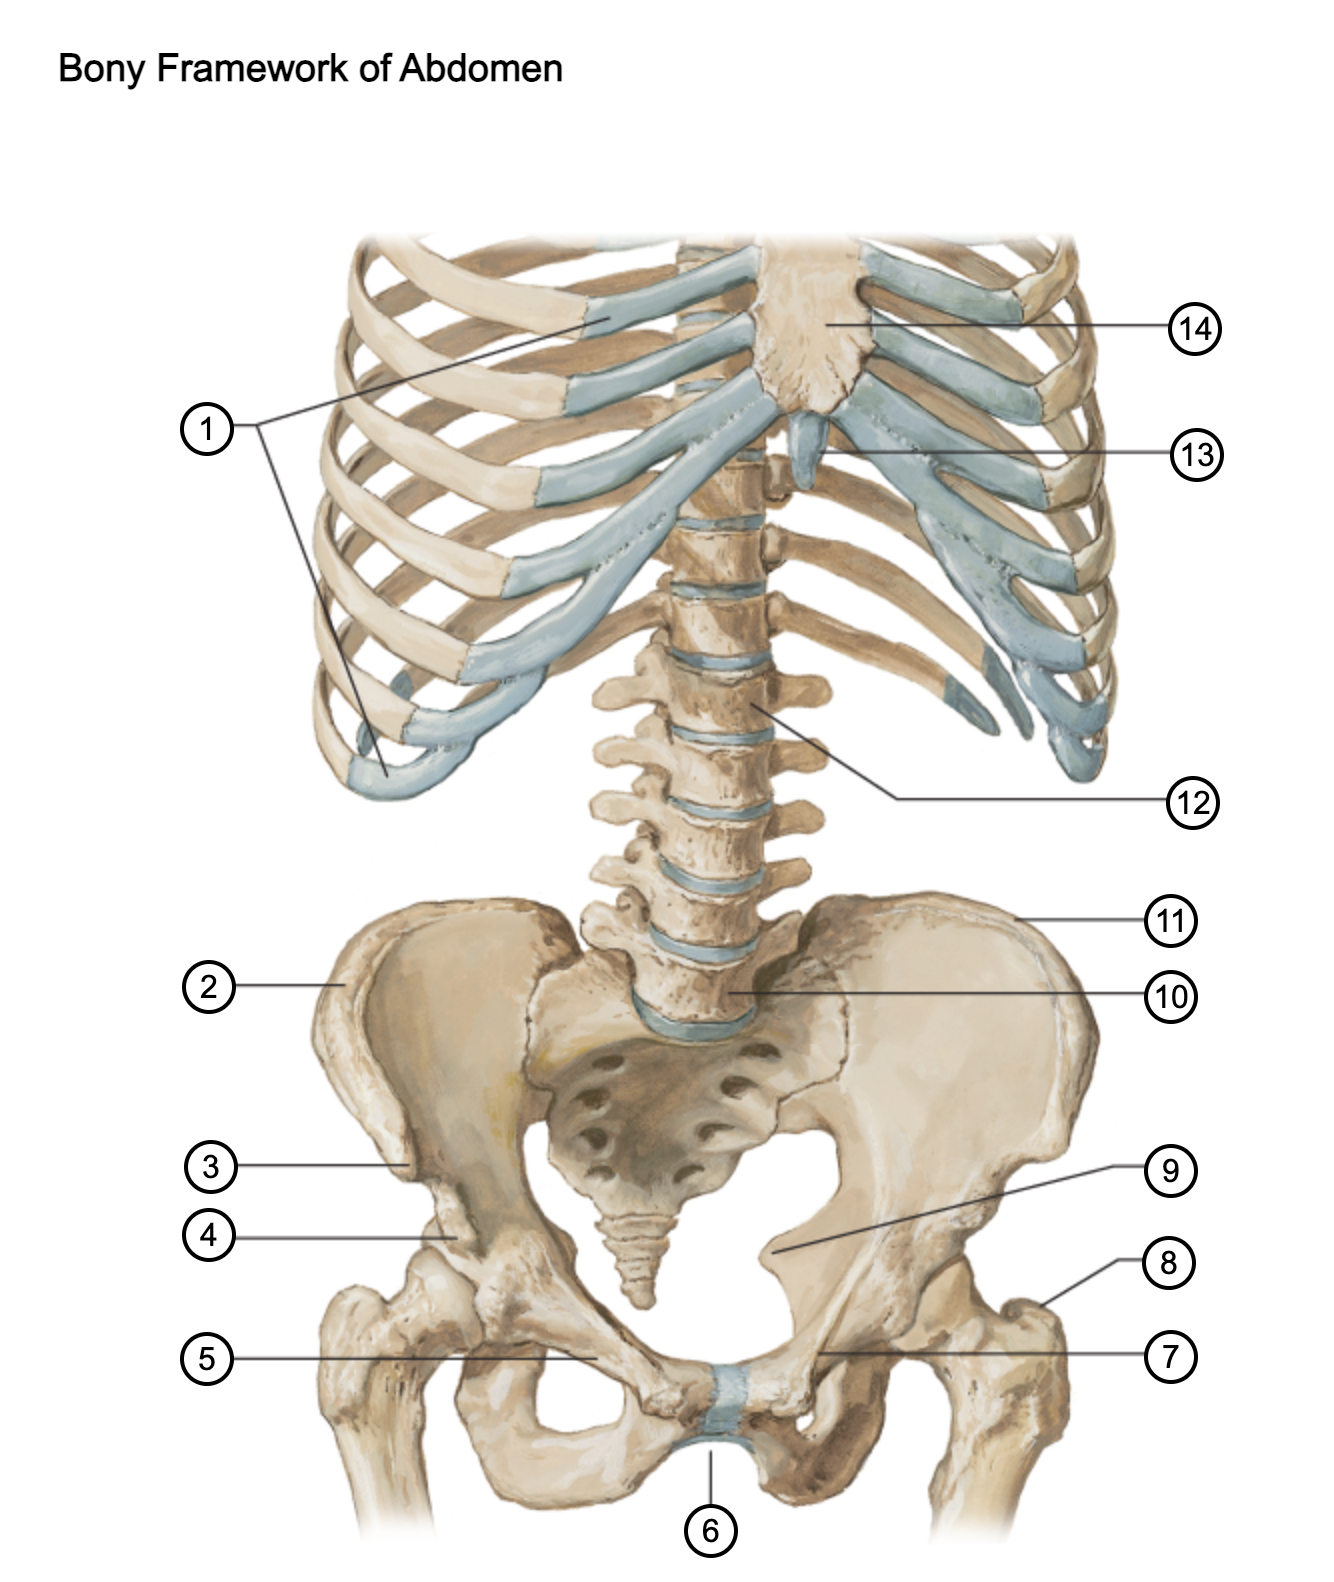

1

costal cartilages

2

iliac crest

3

anterior superior iliac spine

4

anterior inferior iliac spine

5

superior pubic ramus

6

pubic arch

7

pecten pubis

8

greater trochanter

9

ischial spine

10

L5 vertebra

11

iliac crest

12

L1 vertebra

13

xiphoid process

14

body of sternum